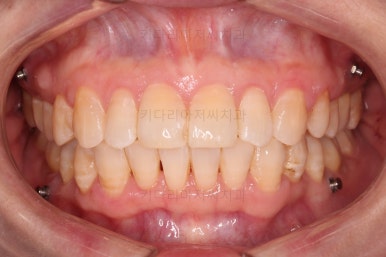

마무리 사진이에요.

치열이 매우 가지런해졌고, 틈도 없고, 앞니의 뻗친 느낌도 사라졌네요.

교합도 좋고요.

삐뚤고 솟구쳐 있던 치열도 가지런하게 되었고, 틈새도 다물어졌으며 뻗쳐 있던 느낌도 개선이 되었어요.

18개월의 기간동안 부산성인교정 많은 점들이 개선되 만족스러운 치료결과였어요.